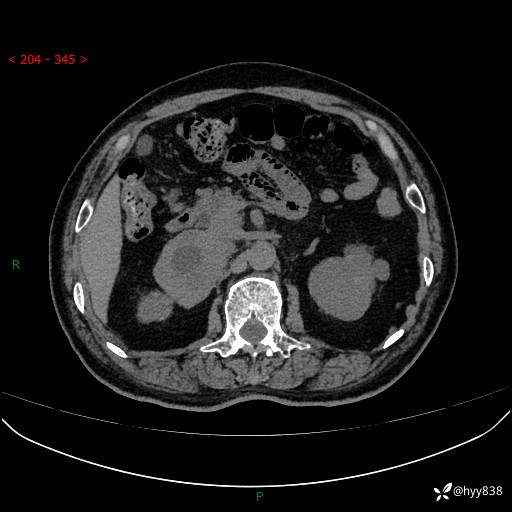

【患者信息】:76岁/男

【主诉】:检查发现右侧肾上腺占位6天

【现病史及既往史】:患者6天前体检发现右侧肾上腺占位,无腰痛,无放射痛,无尿频、尿急、尿痛及肉眼血尿,无畏寒、发热,无恶心、呕吐,今为求进一步治疗,遂来我院就诊,门诊拟“右侧肾上腺占位”收住入院。 起病以来,患者精神、饮食、睡眠可,大小便如常,体力体重无明显变化。

【检查】:肾上腺CT平扫+增强